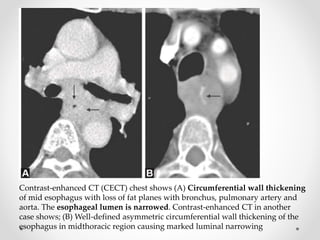

Contrast-enhanced CT (CECT) chest shows (A) Circumferential wall thickening

of mid esophagus with loss of fat planes with bronchus, pulmonary artery and

aorta. The esophageal lumen is narrowed. Contrast-enhanced CT in another

case shows; (B) Well-defined asymmetric circumferential wall thickening of the

esophagus in midthoracic region causing marked luminal narrowing